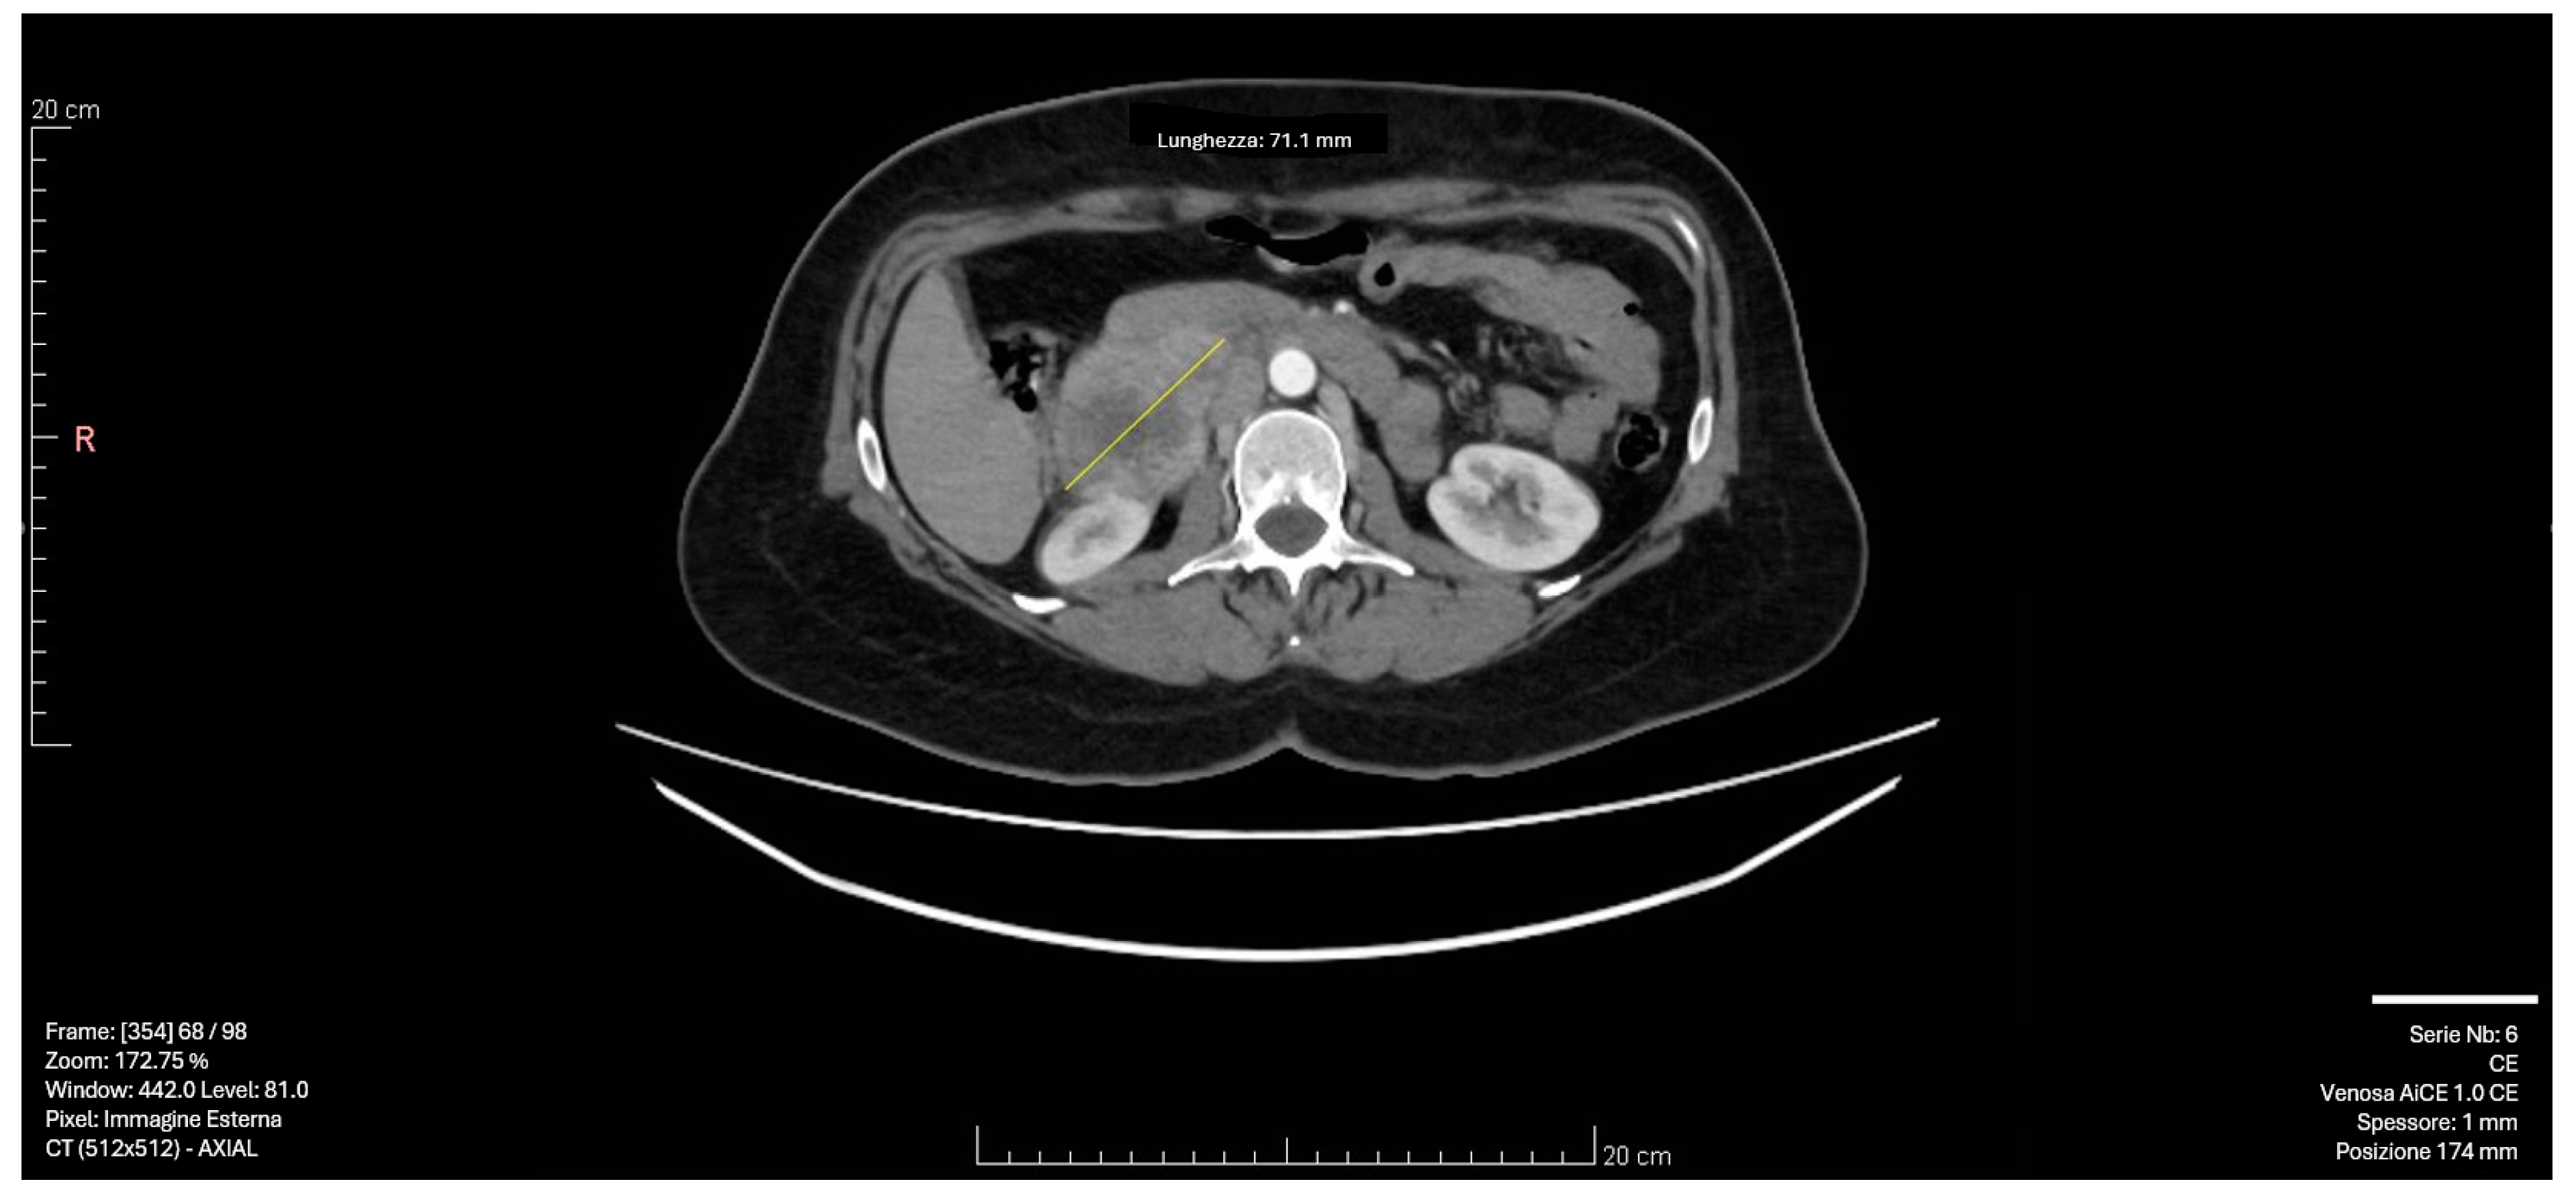

| Our Case Rep | 52 | F | R | 9 × 7 × 6 | None | Laparoscopic Adrenalectomy + Nephrectomy | CT | 12 (alive with liver metastasis) |